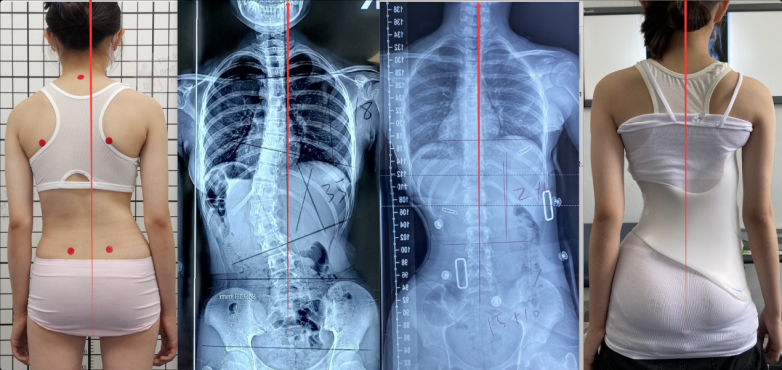

ALS分型体系 极端的不对称性与“过矫正”哲学 GBW支具在外观上比原始色努支具更为“夸张”。它追求的是一种受控的“过矫正”(Overcorrection) 。韦斯博士认为,如果支具仅仅是将脊柱拉直,那么在脱掉支具后,由于软组织的弹性回缩,曲线往往会回弹。只有在发育高峰期将脊柱维持在“镜像位点”(Deformity-Mirror Image),即向弯曲相反的方向过度推挤,才能有效地通过Hueter-Volkmann法则重塑椎体的生长形态 。 这种过矫正不仅体现在Cobb角的度数上,更体现在躯干的整体对称性。临床数据显示,GBW支具的即时入具矫正率往往能超过50%,甚至达到80%-90% 。

GBW支具案例 支具的小型化与“轻量化”设计 原始色努支具常被批评为过于笨重,腋下高度过高,导致佩戴舒适度差,影响青少年患者的依从性 。韦斯博士在设计GBW时,秉承了“减少材料”(Reduction of Material)的哲学 。 通过精确的受力分析,GBW去除了支具上不必要的冗余部分,采用了独特的“半盆地”设计(Hemi-pelvis),显著降低了支具的总高度和体积 。这种“轻量化色努”(Cheneau Light)的概念,使得支具可以更隐蔽地穿在衣服内,极大地改善了患者的心理压力和日常活动能力 。 ALS分类系统:GBW设计的灵魂 支具设计的成败很大程度上取决于对弯曲模式的精准识别。韦斯博士在2010年对原始的施罗斯分类进行了扩展,提出了“增强型莱内特-施罗斯分类”(Augmented Lehnert-Schroth, ALS Classification) 。 ALS分类在临床决策中的应用 ALS系统将脊柱侧弯分为七种特定的功能模式,每一种模式都对应GBW模型库中特定的力学模块 。 ALS 分类代码 | 模式描述 | GBW 支具策略 | 3CH | 功能性3弧,伴明显髋部突出。 | 侧重于胸椎凸侧压力与骨盆对侧推力的协调,稳定骨盆。 | 3CTL | 功能性3弧,顶点位于胸腰段,伴髋部突出。 | 压力中心下移,重点处理胸腰结合部的旋转。 | 3C | 平衡型功能性3弧。 | 整体三维重排,无需大幅度的髋部代偿调整。 | 3CL | 3弧模式,伴长腰段代偿弧。 | 强化胸椎矫正的同时,给予腰椎足够的解旋空间。 | 4C | 功能性4弧,双大弯。 | 将躯干分为独立的四个功能块,设置两组独立的压力-空腔对。 | 4CL | 4弧模式,腰弯为主。 | 优先处理腰椎旋转,通过骨盆模块实现底层稳定。 | 4CTL | 4弧模式,胸腰弯为主。 | 介于胸腰结合部处理与双弯处理之间的过渡策略。 |